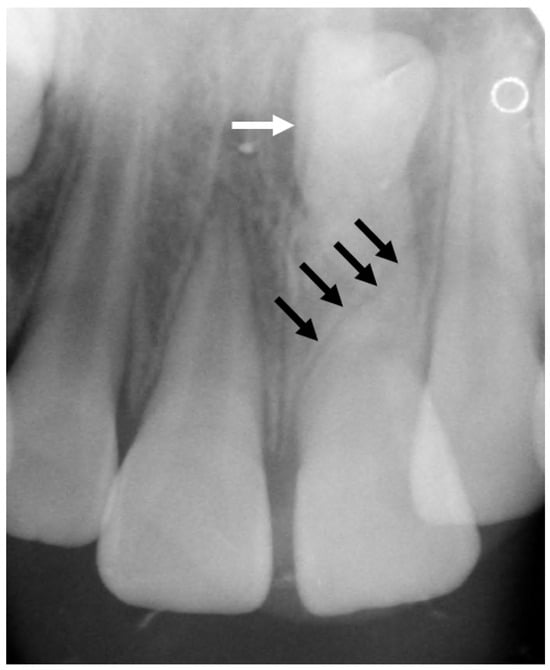

3.5.2. Dental Decay Radiologic Correlations

3.5.4. Periodontal Disease Radiologic Correlations